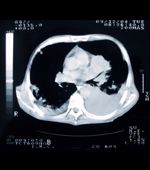

The new trial will include 10,000 participants who have smoked the equivalent of 20 cigarettes per day for more than 20 years; half will undergo testing with EarlyCDT-Lung followed by computed tomography scans if the blood test is positive, while the other half receive current standard of care treatment. The trial will start by the end of 2012, and results are expected by the end of 2014.

Screening for lung cancer has not achieved cost-effectiveness in the past, though there has been a move toward screening recently. The National Lung Screening Trial enrolled more than 53,000 high-risk individuals at 33 centers in the United States, and found that low-dose CT screening can reduce mortality from lung cancer. The rate of death from any cause was 6.7% lower in those who underwent CT screening compared with a standard radiography group. The rate of death due to lung cancer alone was reduced by 20%. There is no suggestion, though, that such screening can be cost-effective. The most recent recommendation from the U.S. Preventive Services Task Force, from 2004, says that the “evidence is insufficient” to recommend for or against screening with low-dose CT or other methods.

According to Oncimmune, EarlyCDT-Lung can detect about half the cancers in a screened population and will reduce the number of people who need to undergo CT scans to 7%. With half the cancers restricted to a 7% chunk of the overall screened group, the company thinks it will be a cost-effective screening method.